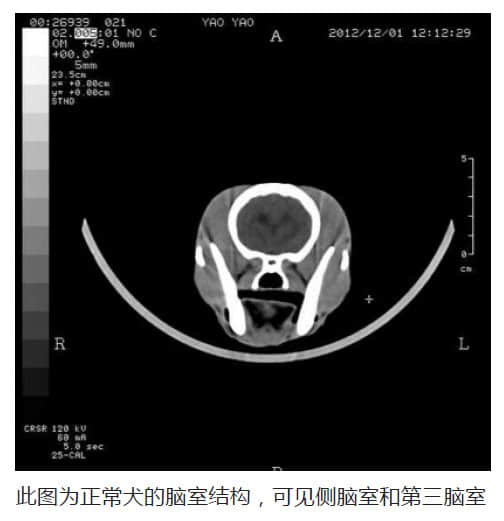

C T 影 像所见: 双侧大脑半球对称,灰白质对比正常,未见局灶性密度异常,中线结构居中,双侧侧脑室、第三脑室及四脑室对称性中度扩大,侧脑室宽1.33cm, 侧脑室的上角和下角通路异常增宽,幕下小脑、脑干无异常。囟门未闭合,宽1.36cm。侧脑室体部宽度指数:4.11/2.66=1.5。

CT影像所见:颅骨三处如缺,最宽处0.9cm。双侧大脑半球对称,灰白质对比正常,未见局灶性密度异常,中线结构居中,双侧侧脑室前角、第三脑室 及四脑室对称性中度扩大,侧脑室宽1.33cm,右侧侧脑室的上角和下角通路异常增宽,幕下小脑、脑干无异常。囟门未闭合,宽0.6cm。侧脑室体部宽度 指数:3.98./2.46=1.62。

脑积水的诊断标准

在宠物诊疗上没有一个准确的标准来判断脑积水,但通过许多病例的积累于鉴别,得出一个规律,利用侧脑室体部宽度指数来判断脑水肿。但有时候也可以依靠大量脑水肿病例的经验来判: